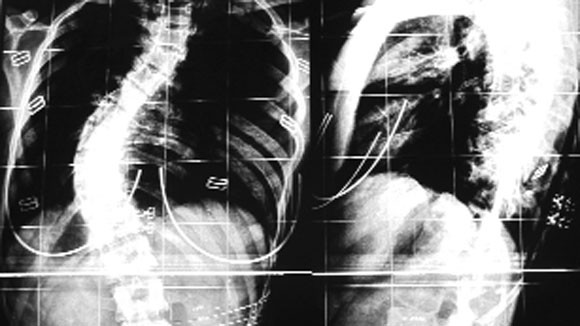

Phim X-quang của một bệnh nhân bị vẹo cột sống 70 độ

Tại khoa Phẫu thuật cột sống - BV Việt Đức những năm gần đây, số bệnh nhân đến khám, điều trị cong vẹo cột sống ngày càng tăng và hầu như tuần nào cũng có bệnh nhân phẫu thuật. Thậm chí từ đầu năm đến nay, BV đã phẫu thuật cho khoảng 10 ca bị vẹo cột sống đã sang Singapore phẫu thuật với chi phí lên đến 30.000-40.000USD nhưng khi về nước gặp biến chứng nặng và phải mổ lại. Có mặt tại BV, chúng tôi gặp 2 bệnh nhân vừa được phẫu thuật chữa vẹo cột sống xong và đang điều trị hậu phẫu. Trong đó có một bệnh nhân nữ 20 tuổi, ở Sóc Sơn (Hà Nội), hiện đang là sinh viên, có độ vẹo cột sống trước khi mổ lên đến 70% khiến cơ thể bị “lùn” mất 7, 8 cm.